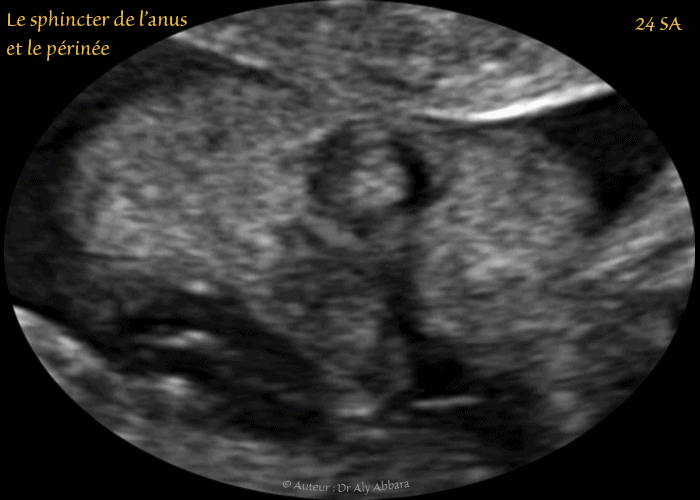

• Images échographiques montrant l'aspect normal du sphincter de l'anus et du périnée à 24 et à 28 SA

• Sphincter : muscle en forme d'anneau qui ferme ou resserre un orifice du corps. Dans cet article, il s'agit du canal anal.

• Périnée : la région anatomique située entre l'anus et les parties génitales externes.